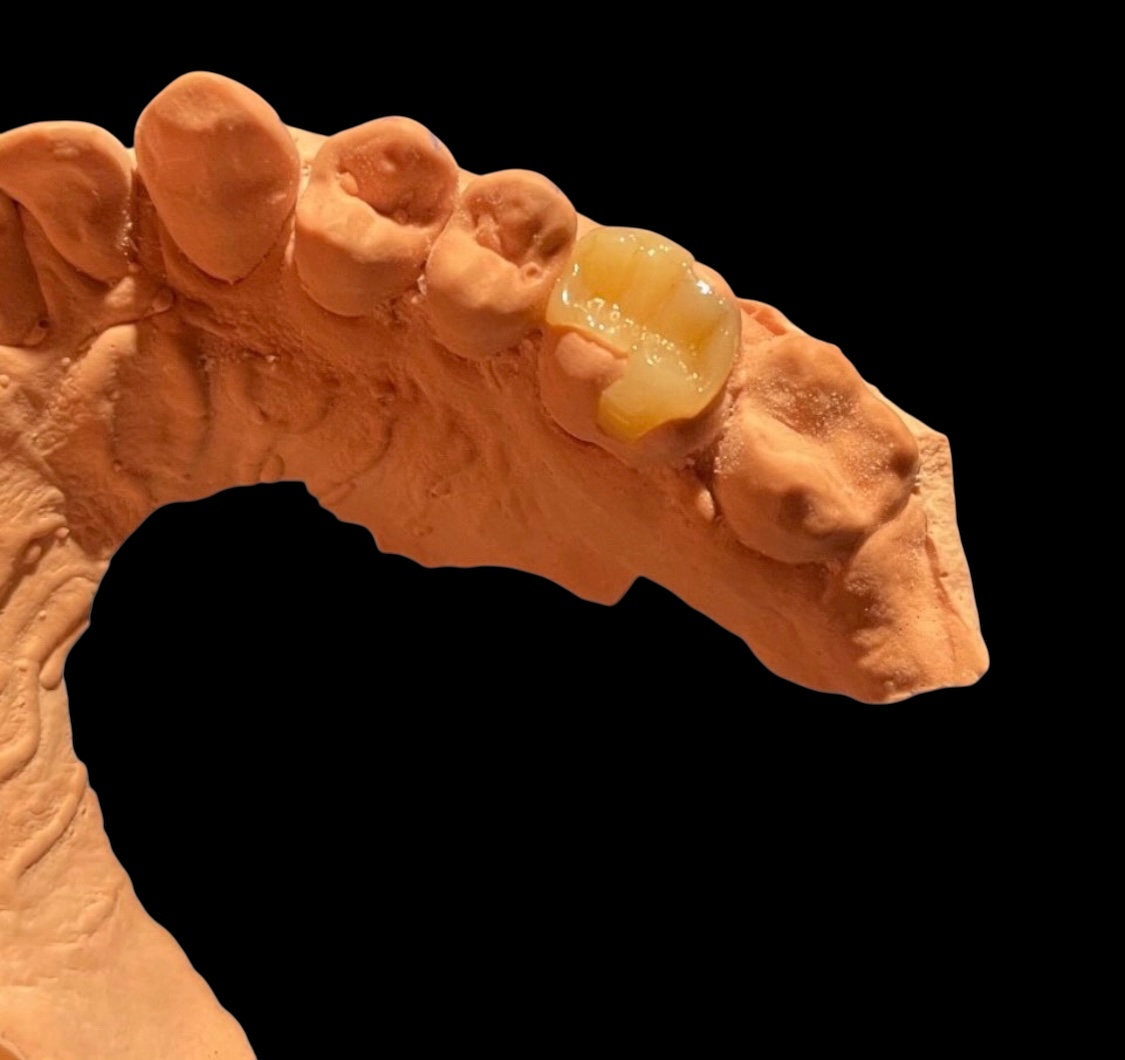

Producto 1

Descripción de ejemplo para el producto 1.